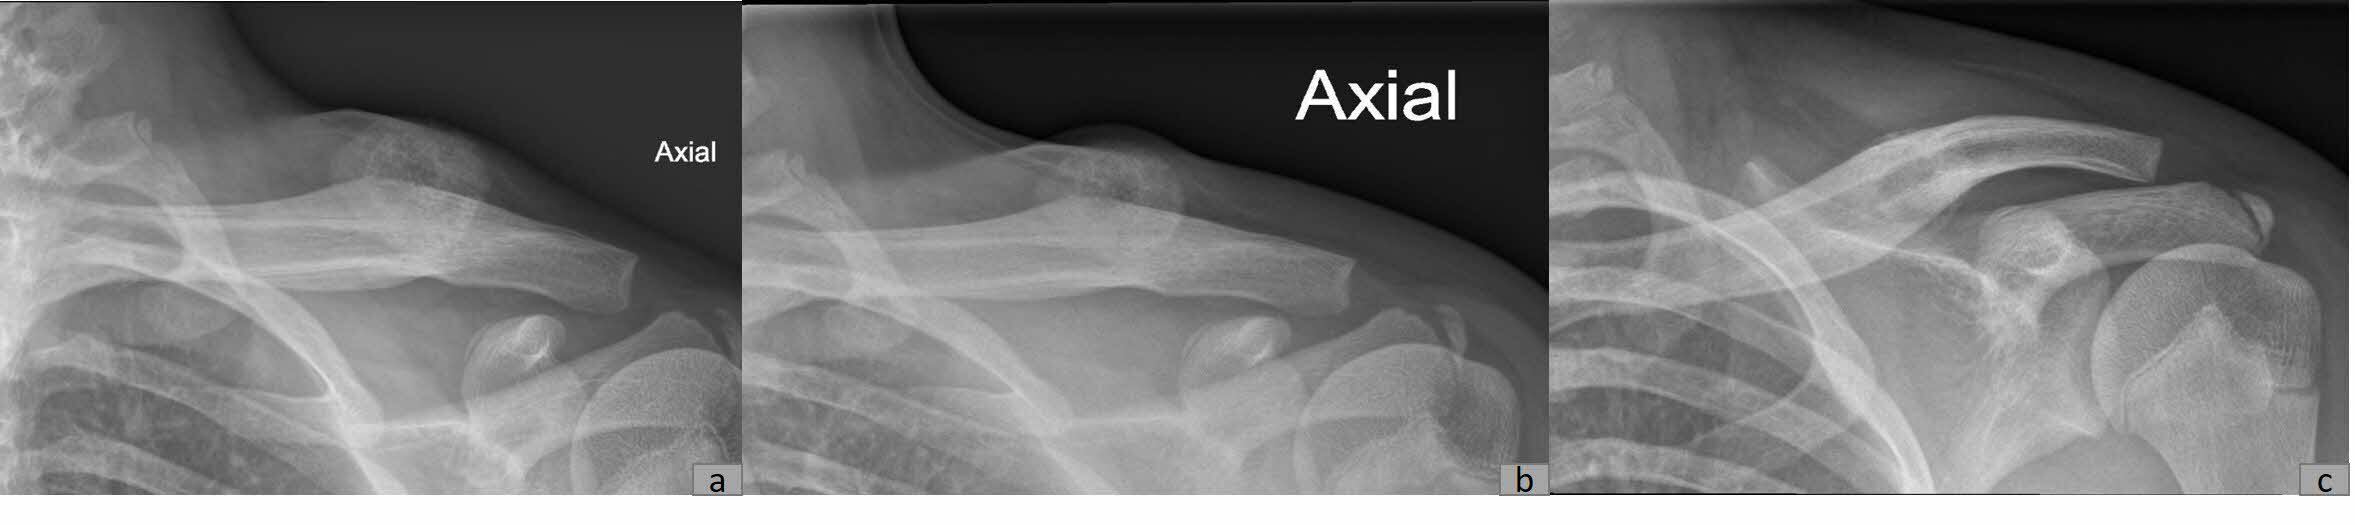

Plain radiography revealed a calcified mass with associated periosteal reaction along the left clavicular shaft (Figure 1). An MRI scan was also done and reported an avidly-enhancing T1w-isointense and T2w-hyperintense lesion in the middle-distal third of the left clavicle, measuring approximately 3.1cm x 2.8cm x 2.3cm (Figure 2). In certain areas, the lesion was inseparable from the adjacent periosteum (Figure 3), which itself was significantly thickened and enhancing. There was also increased T2W marrow edema with enhancement and some adjacent soft tissue swelling. No associated fracture was noted. The MRI report was suggestive of a malignant lesion such as soft tissue sarcoma.

Subsequently, the patient was referred to musculoskeletal oncology given the high suspicion of malignancy. Conservative treatment was adopted for this patient, including a 3 months prescription of Indomethacin and continual radiographic monitoring. Spontaneous resolution of the mass was observed over the next six months, as evidenced by plain radiography (Figure 5). At the fifth month of follow-up, the patient was asymptomatic and exhibited normal function with a full range of motion in the left shoulder. Consequently, the patient was given an open dated review.